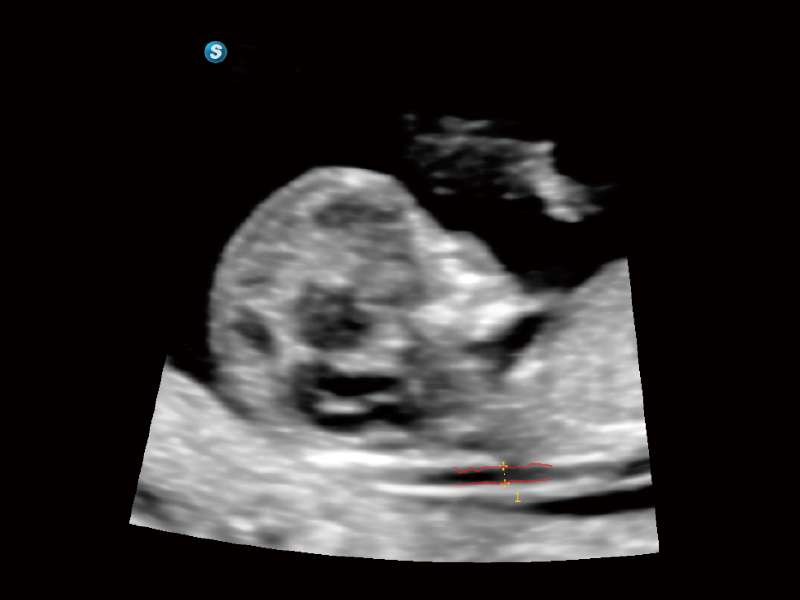

作為開(kāi)立醫(yī)療全新打造的超高端旗艦超聲產(chǎn)品,從探頭抬起喚醒開(kāi)啟掃查到多維探頭發(fā)射接收,通過(guò)先進(jìn)的場(chǎng)成像發(fā)射、自適應(yīng)聚合重建等技術(shù),基于RF Data原始射頻數(shù)據(jù)在圖像生成、高端功能等方面實(shí)現(xiàn)突破,為婦產(chǎn)科、兒科提供全方位臨床解決方案。

夢(mèng)溪?P80以“關(guān)愛(ài)女性”為基石,提供全方位的解決方案,量身定制以滿(mǎn)足女性的健康需求,涵蓋婦科、生殖健康檢查、產(chǎn)前篩查及產(chǎn)后康復(fù)等領(lǐng)域。